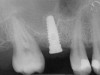

A 53-year-old female was referred for evaluation of a fracture of tooth No. 24. The tooth had been treated endodontically 5 years prior. The radiograph revealed a complete fracture of the tooth involving the crown (Figure 12). Tooth extraction and immediate placement of a an implant that was 10 mm in length and 3.75 in diameter was planned.

At the time of surgery, the tooth was extracted without harvesting any mucosal flap because the implant site was prepared by means of a pilot drill bur (Figure 13) and alternating osteotomes (Figure 14A and Figure 14B). The implant was positioned and showed primary stability. The implant was loaded 2 days after surgery. Then, splinted PFM crowns supported by custom gold abutments were delivered. At 6 months posttreatment, the radiograph revealed no bone resorption and the clinical result was optimal (Figure 15A and Figure 15B).

Figure 12  Preoperative radiograph shows fractured tooth No. 24.

Figure 15B Posttreatment radiograph, 6 months after the initial surgery.

Figure 15  Posttreatment radiograph, 6 months after the initial surgery.

Figure 15b